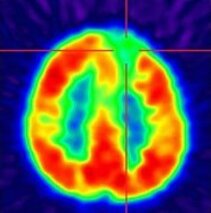

Bild oben: Positronenemissionstomographie (PET) mit der radioaktiven Aminosäure 18FET bei einem Patienten mit einem links temporalen (im Bild rechts) Glioblastom. Der Hirntumor (farbkodiert in grün bis rot) weist gegenüber dem gesunden Hirngewebe (farbkodiert in dunkel- bis hellblau) eine deutlich erhöhte Aminosäureaufnahme auf und lässt sich so für die weitere Therapie optimal abgrenzen.

(das Bild oben wurde freundlicherweise von Prof. Dr. med. Philipp Tobias Meyer, Klinik für Nuklearmedizin, zur Verfügung gestellt)

Bild links: FDG-PET zum Nachweis hypometaboler Areale (mit freundlicher Genehmigung der Klinik für Nuklearmedizin, Direktor: Prof. Meyer).